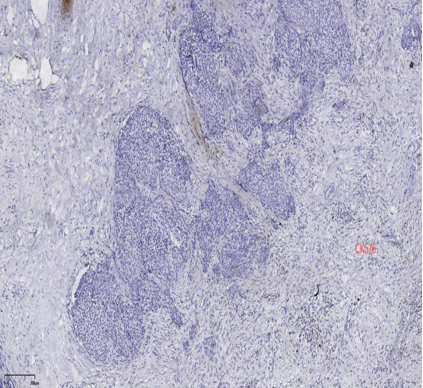

具有神经内分泌表达:CgA、Syn(约70%的比例,阳性细胞表达不等)

CK5/6、CKH-,可斑驳性的残留

肌上皮内-,导管周可-可+